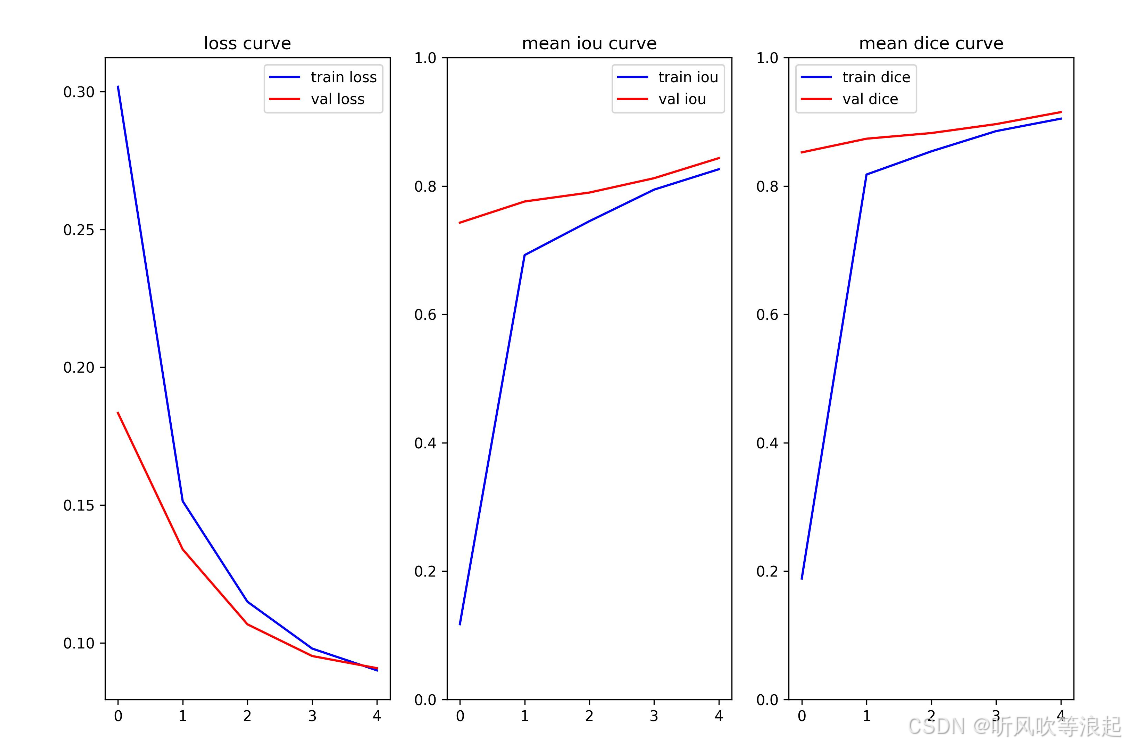

这里仅仅训练了5个epoch用于测试代码的可行性,指标不做参考

[epoch:0/4]

train: 100%|██████████| 128/128 [00:30<00:00, 4.17it/s, dice=0.504, iou=0.337, loss=0.177]

valid: 100%|██████████| 32/32 [00:05<00:00, 5.73it/s, dice=0.839, iou=0.723, loss=0.178]

train loss:0.3018 train mean iou:0.1173 train mean dice:0.1885

val loss:0.1834 val mean iou:0.7428 val mean dice:0.8523

[epoch:1/4]

train: 100%|██████████| 128/128 [00:30<00:00, 4.23it/s, dice=0.742, iou=0.59, loss=0.132]

valid: 100%|██████████| 32/32 [00:05<00:00, 5.68it/s, dice=0.857, iou=0.75, loss=0.131]

learning rate:0.00009055

train loss:0.1514 train mean iou:0.6923 train mean dice:0.8178

val loss:0.1339 val mean iou:0.7758 val mean dice:0.8736

[epoch:2/4]

train: 100%|██████████| 128/128 [00:30<00:00, 4.26it/s, dice=0.862, iou=0.757, loss=0.103]

valid: 100%|██████████| 32/32 [00:05<00:00, 5.77it/s, dice=0.874, iou=0.776, loss=0.103]

train: 0%| | 0/128 [00:00<?, ?it/s]learning rate:0.00006580

train loss:0.1149 train mean iou:0.7451 train mean dice:0.8539

val loss:0.1067 val mean iou:0.7897 val mean dice:0.8824

[epoch:3/4]

train: 100%|██████████| 128/128 [00:30<00:00, 4.23it/s, dice=0.891, iou=0.803, loss=0.0956]

valid: 100%|██████████| 32/32 [00:05<00:00, 5.74it/s, dice=0.888, iou=0.799, loss=0.0919]

learning rate:0.00003520

train loss:0.0979 train mean iou:0.7943 train mean dice:0.8854

val loss:0.0952 val mean iou:0.8121 val mean dice:0.8963

[epoch:4/4]

train: 100%|██████████| 128/128 [00:29<00:00, 4.30it/s, dice=0.908, iou=0.831, loss=0.0893]

valid: 100%|██████████| 32/32 [00:05<00:00, 5.67it/s, dice=0.904, iou=0.825, loss=0.0901]

learning rate:0.00001045

train loss:0.0900 train mean iou:0.8261 train mean dice:0.9048

val loss:0.0908 val mean iou:0.8434 val mean dice:0.9150

验证集上表现最好的epoch为: 4